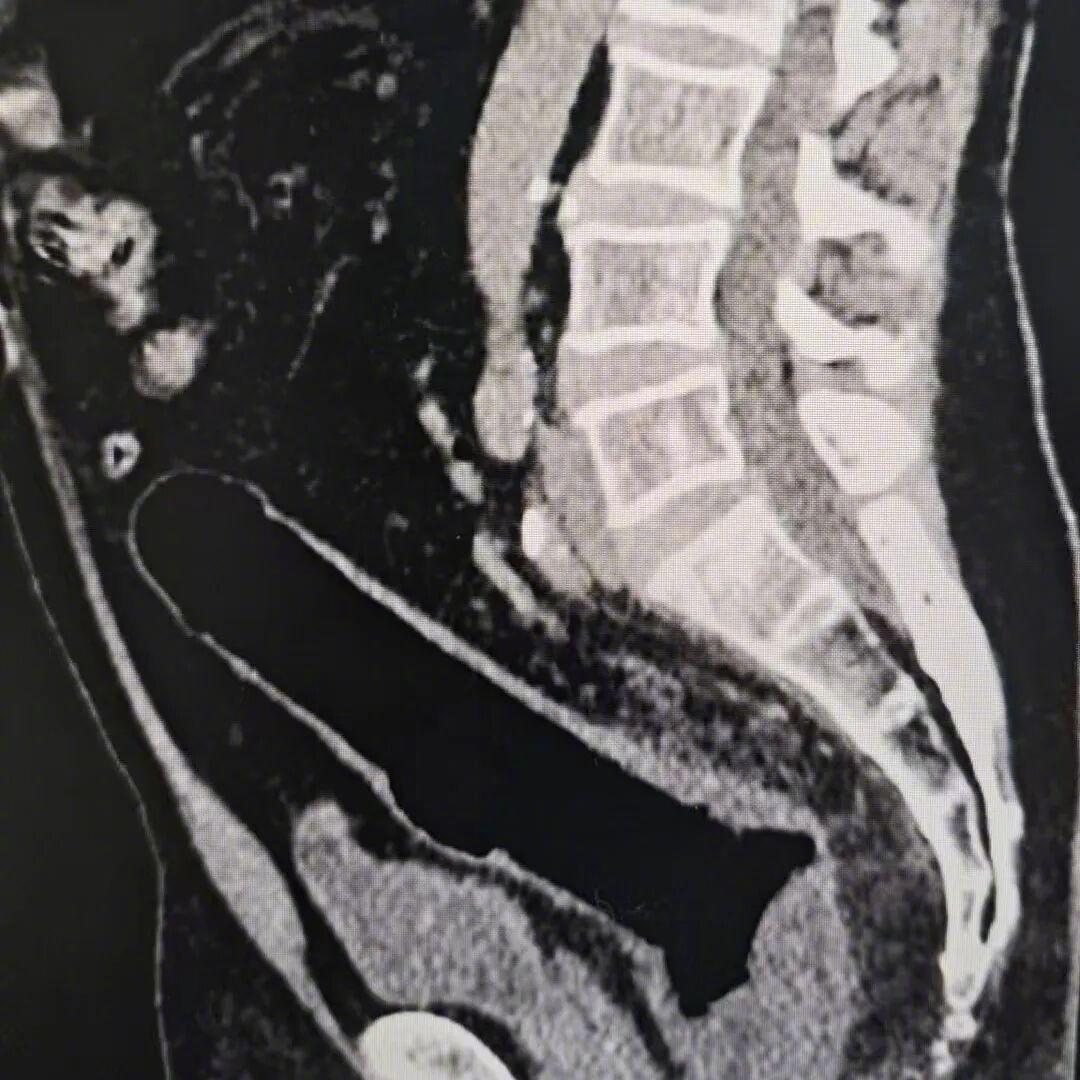

谁知两三天过去,异物不仅没有排出,患者还出现了明显腹痛。再次就医做 CT 检查后,结果显示肠道已经穿孔,原本简单的异物取出问题,彻底演变成了急症。